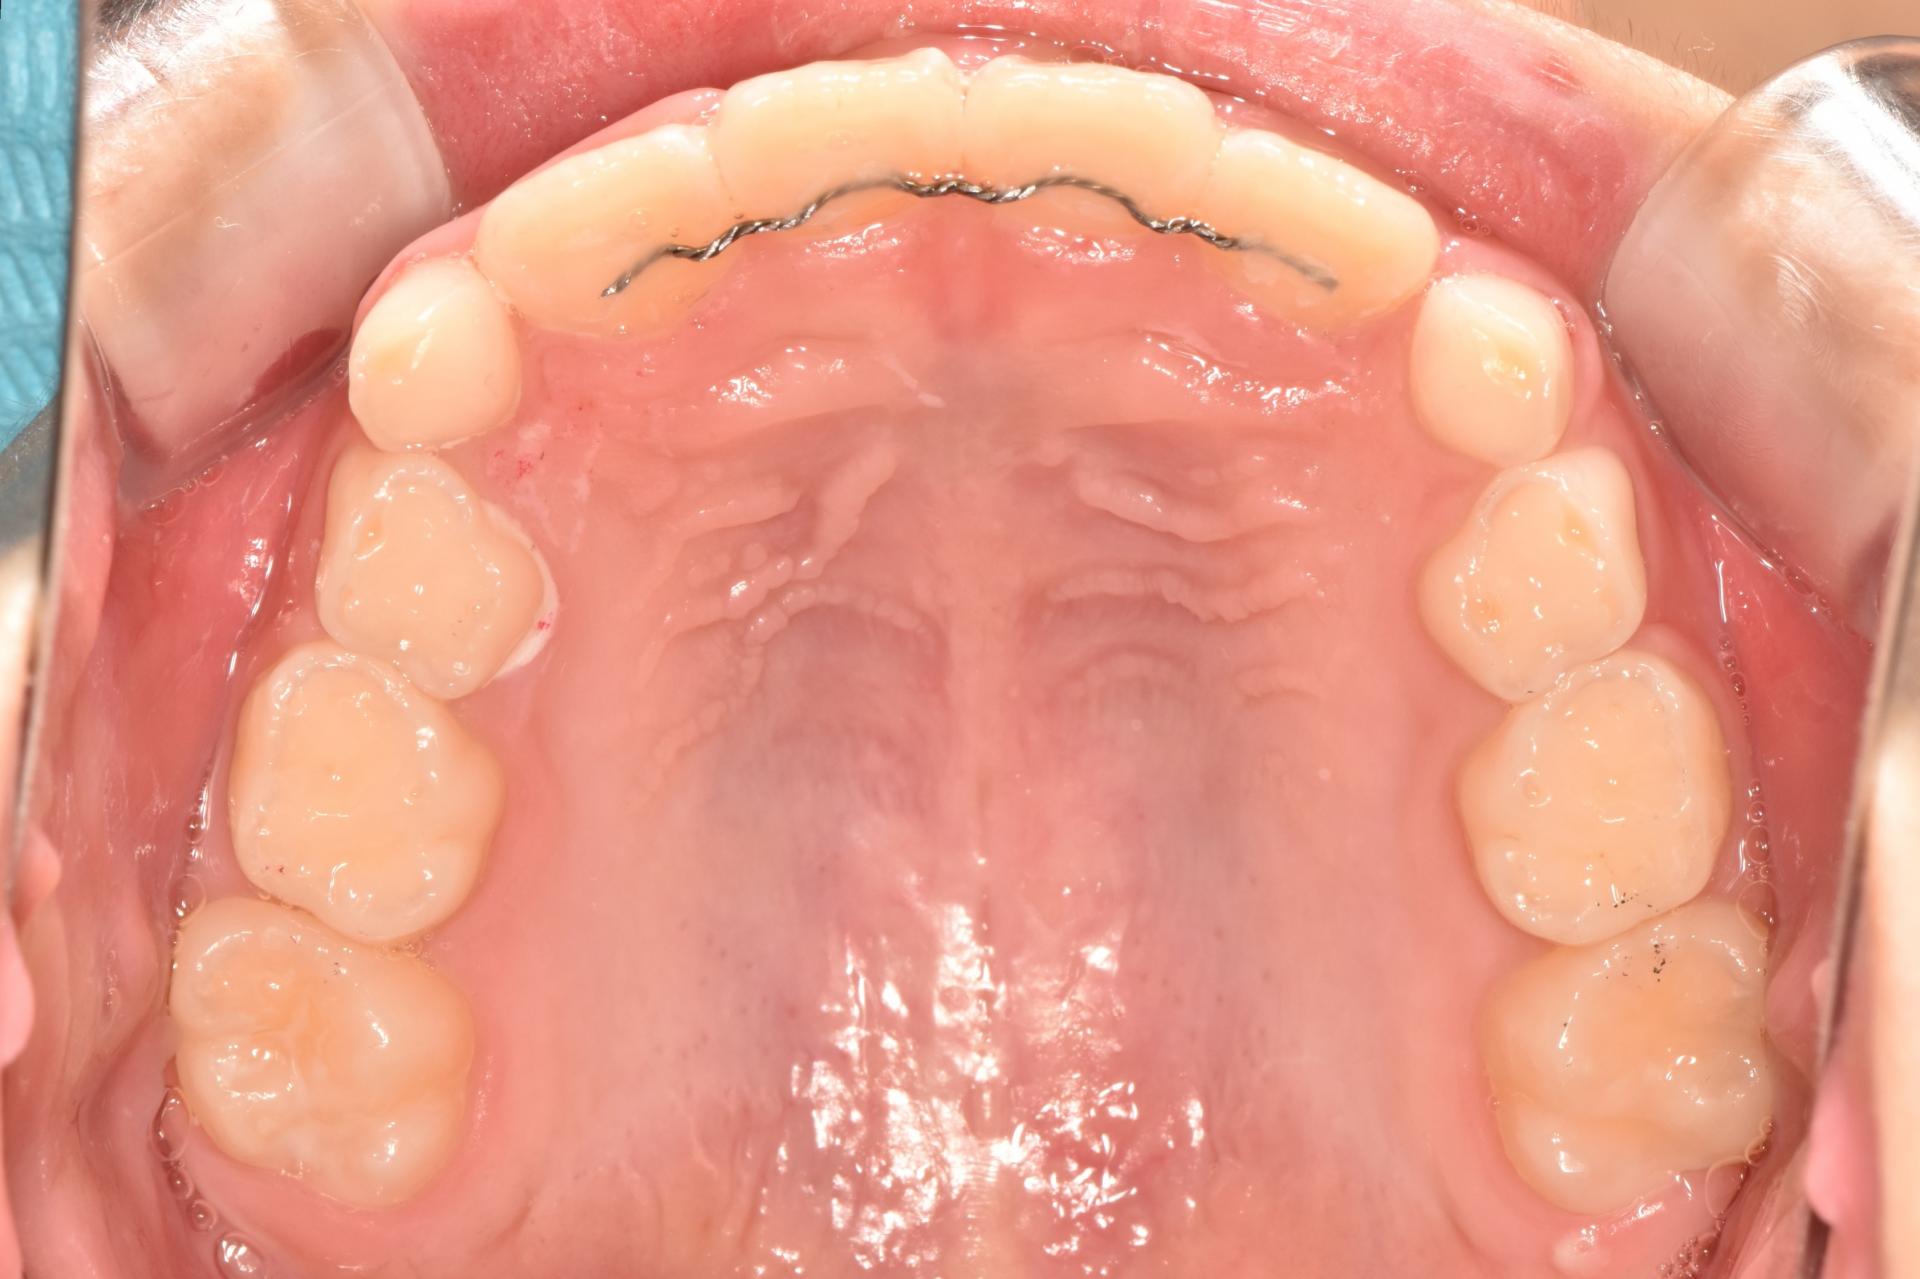

오늘 소개 드릴 케이스는, 서울효앤주니어치과에서 충치치료도 다 하고 정기검진 중, 앞니가 삐뚤게 나고 있어 교정을 하게된 아이입니다.

초진입니다. 위아래 앞나의 공간부족으로 이가 삐뚤뺴뚤 나고있고, 앞니도 뻐드려져있네요.